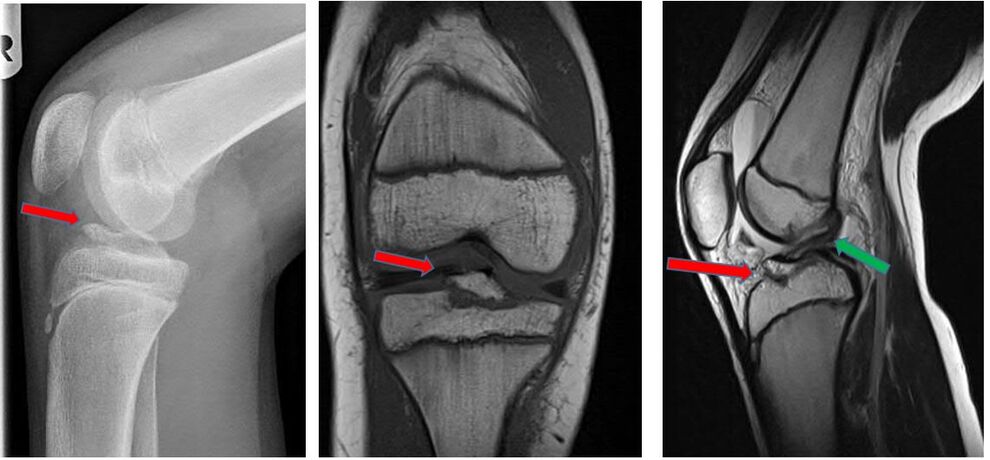

Eine Sonderform der Kreuzbandverletzung ist der knöcherne Ausriss des Bandes. Dabei kommt es bei der Verletzung nicht zu einer Ruptur des Bandes, sonders das Kreuzband reist mit einem Knochenstück ab. Meist ist dieser Ausriss dabei am Schienbeinkopf lokalisiert. Besonders gefährdet sind Kinder und Jugendliche, da bei diesen der Knochen meist weicher als die Bandstruktur ist. Die Symptome und Beschwerden entsprechen einer Kreuzbandruptur. Oft können die Verletzten das Bein nicht richtig strecken, da das Knochenstück einklemmt. Diese Verletzung ist im Gegensatz zu einer Kreuzbandruptur oft auch im normalen Röntgenbild des Kniegelenkes zu sehen. Zur Sicherung der Diagnose und um nach eventuellen Begleitverletzungen zu suchen, erfolgt oft ein MRT und manchmal auch eine Computertomographie (CT).